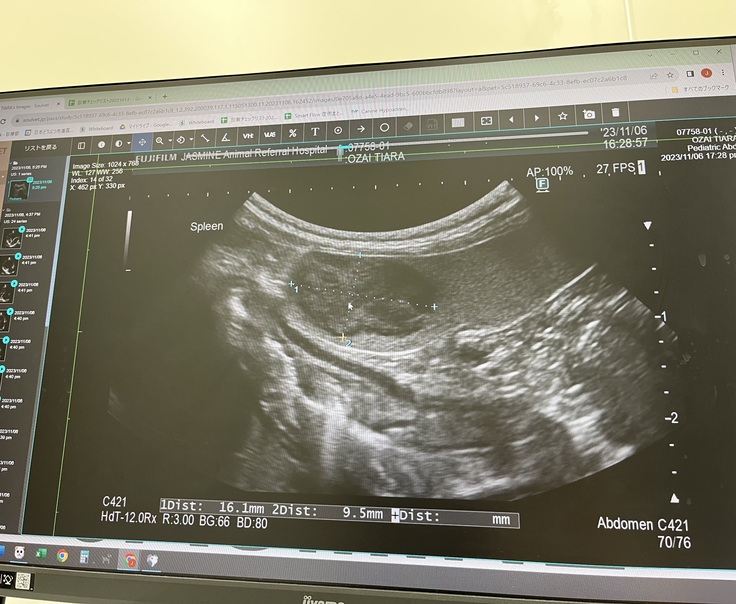

▼脾臓のリンパ腫について

2023.11.06

僧帽弁閉鎖不全症の術前検診の際に

脾臓のリンパ腫が見つかりました。

2023.11.15に

細胞診の検査を受け

やはりリンパ腫の疑いが高いとの事で

摘出手術を検討する事になりました。